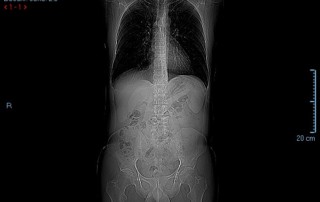

Scan uitslag met afbeeldingen

Nou… daar gaan we dan. Opgewekt met lood in de schoenen naar Amsterdam, naar het Antoni van Leeuwenhoek (AvL) ziekenhuis. De uitslag na 9 weken chemo… […]